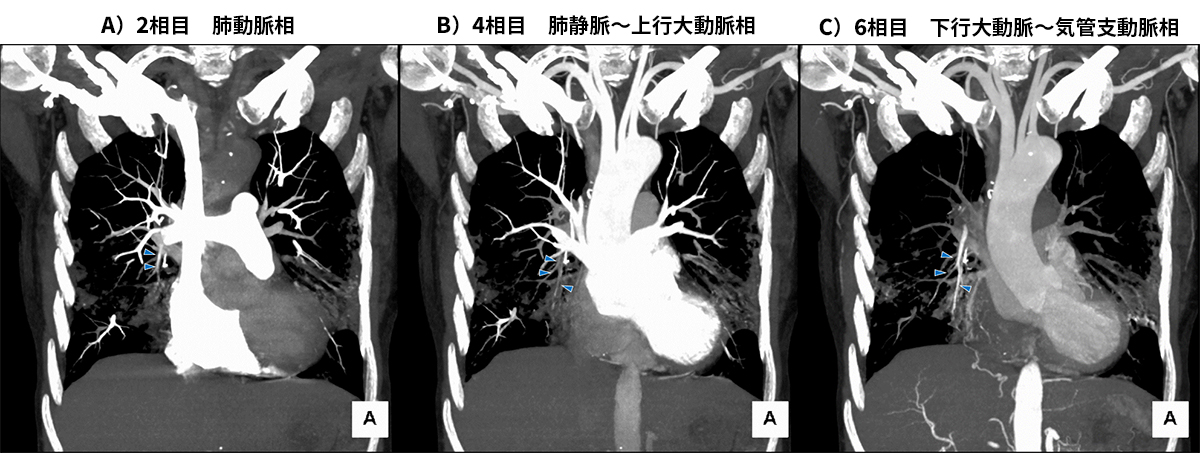

シャトルCTでは右気管支動脈、左気管支動脈から分岐する右気管支動脈の拡張蛇行、右内胸動脈の拡張と分枝の拡張蛇行、下横隔動脈の拡張蛇行を認めた (図2) 。また大動脈相の後期で右肺動脈への造影剤の逆流を認め、いわゆるBA-PAシャントの存在が疑われた (図3) 。以上の結果から喀血に対して気管支動脈等の塞栓術が適応と判断しカテーテル治療を行った。

図3 冠状断のMIP再構成画像

A)の肺動脈相で他の肺動脈よりは弱い造影効果をもつ肺動脈右A5(►)がB)の肺静脈相では造影効果が消失し、C)の下行大動脈相では他の肺動脈と異なり肺動脈右A5に強い造影効果を認める。これは気管支動脈(もしくは他胸郭周囲の体循環系動脈)とのシャント血流があるため、肺動脈相では体循環系からの逆流で他の肺動脈に比べ造影効果がやや低下し、大動脈相で気管支動脈からシャントを経て造影剤が肺動脈に逆流するためである。